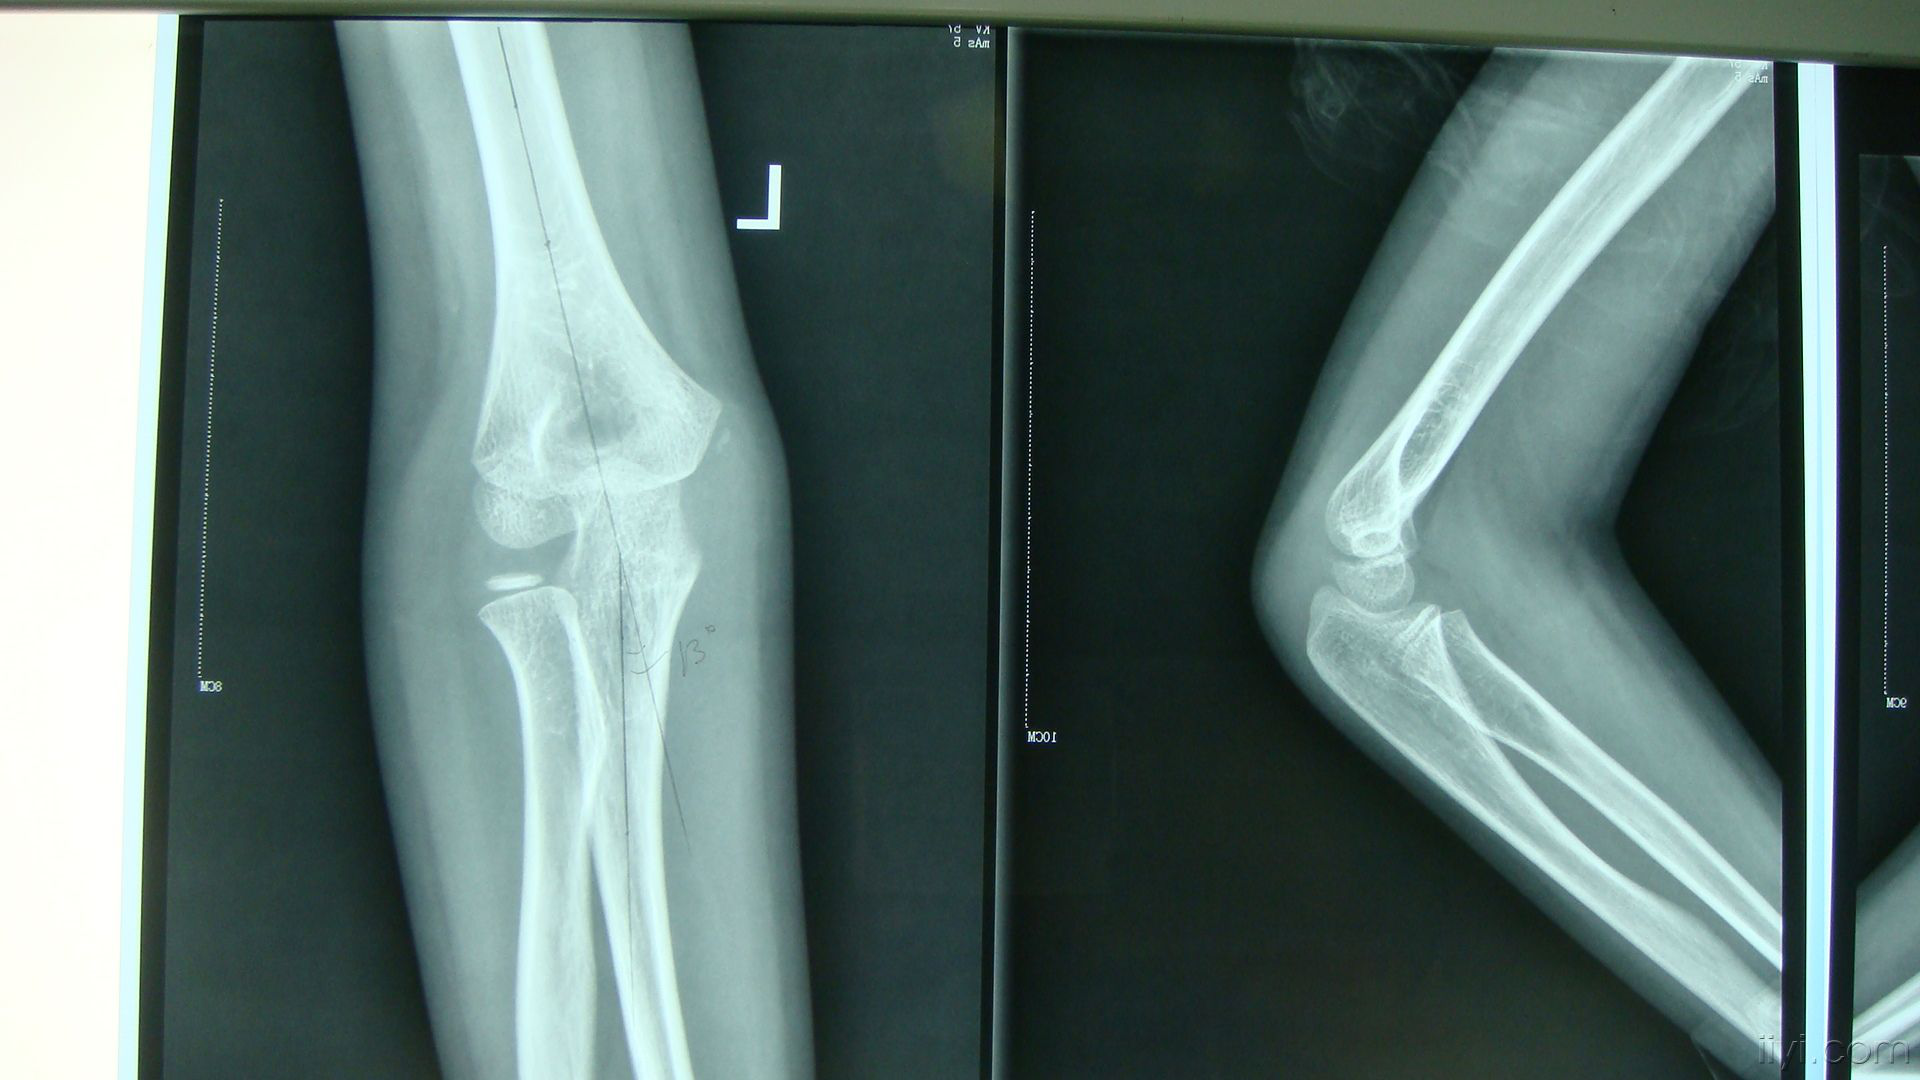

浅谈儿童肱骨外髁骨折

一例肘外翻,滑车畸形,肘管综合征 [病例帖]

王某,东阳人做装修30余年,近几年发现自己胳膊肘弯不起来,也伸不直